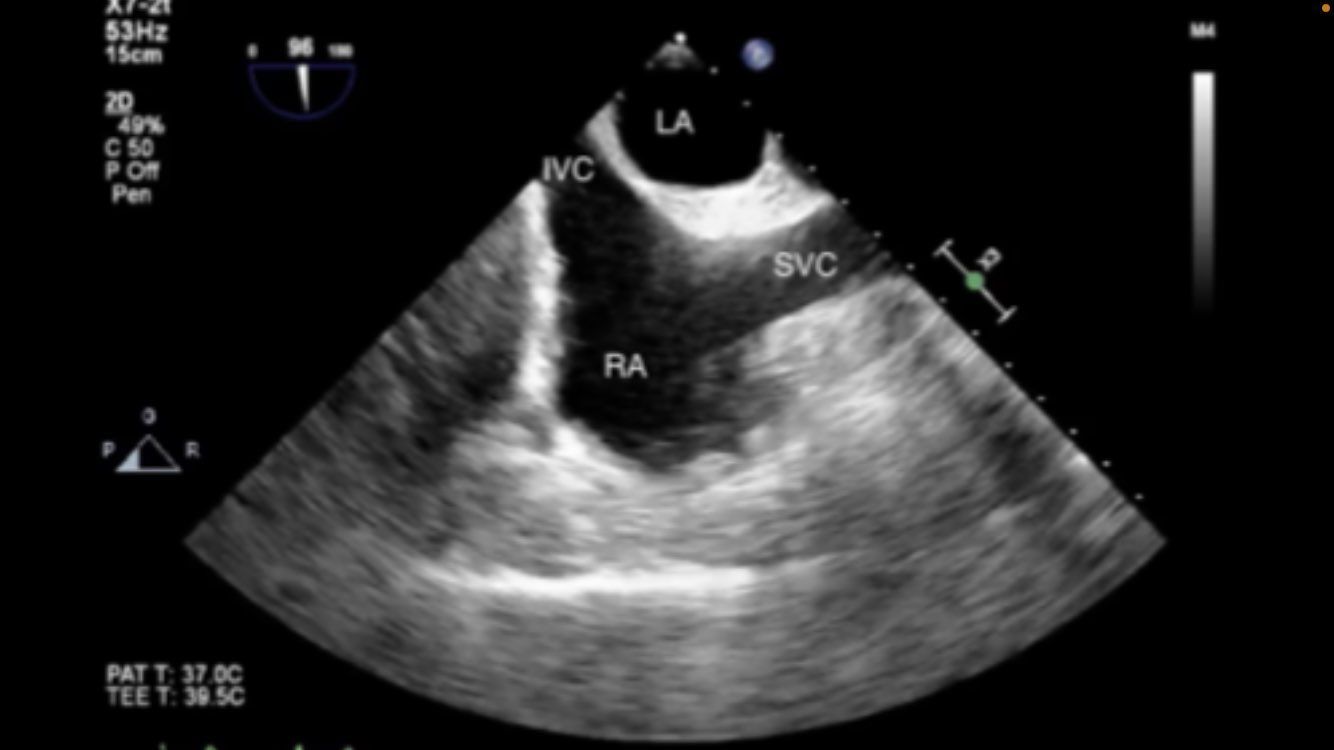

Bicaval view

mid-esphageal bicaval